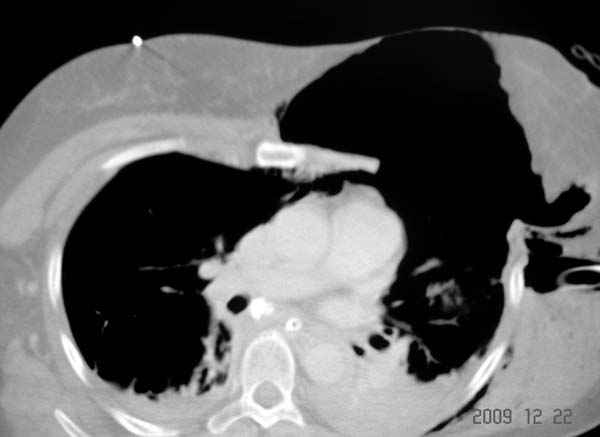

К нам поступила больная 56 лет после автоаварии в бессознательном состоянии, которая срочно заинтубирована в приемном отделении и сделаны необходимые исследования. Данные КТ и рентген показали перелом дистального бедра и Dissociation upper extremity - закрытый отрыв левой верхней конечности на уровне грудинно-ключичного сочленения и множественные переломы ребер.

На поверхности грудной клетки из-за полного разрыва грудной мышцы под кожей заметно биение сердца и след от ремня безопасности. Грудная клетка расширена из-за смещения верхней конечности вверх и латерально. Признаков васкулярного повреждения нет, и из-за отсутствия сознания не смогли определить наличия повреждения нервов.

Срочно в операционной наложен наружный фиксатор и травма хирургом поставлены трубки в плевральную полость.

На седьмые сутки нами совместно с торакальным хирургом сделана операция по фиксации грудинно-ключичного сочленения и переломов ребер.

После кожного разреза обнаружили полный разрыв грудной мышцы и повреждение перикард от уровня второго до восьмого ребер. Хирург находился с нами и после нашей работы зафиксировал повреждение перикарда и разрыв грудной мышцы.